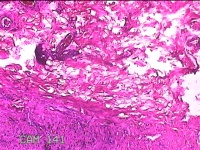

左侧手背结节

性别

男

年龄

43岁

临床诊断

皮下结节

一般病史

患者于近1个月来发现左侧手背一结节,伴局部隐痛不适,无发热。

标本名称

大体所见

灰白暗红色结节1.2x0.3x0.2cm一个,表面光滑。

疑似 :血栓形成。